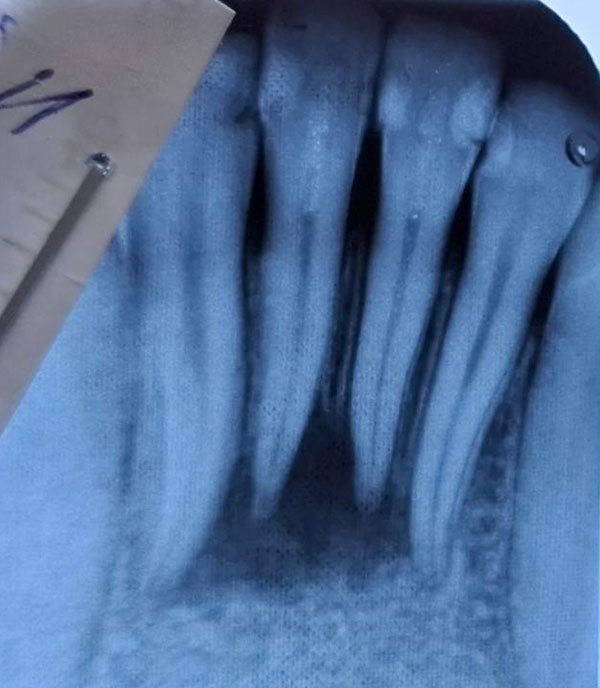

На интраоральной радиограмме: зубы 3.1, 4.1 дефекты пломб, кариозные полости в пределах околопульпарного дентина, сообщающиеся с полостью зуба, зуб 3.2 под пломбой. Зуб 4.2 кариозная полость в пределах околопульпарного дентина, сообщающаяся с полостью зуба. Разрежение костной ткани в проекции верхушек корней 3.1, 3.2, 4.1, 4.2 с нечеткими контурами(20×18 мм). Пространство периодонтальной связки в апикальной трети 4.1, 3.1 не прослеживается.